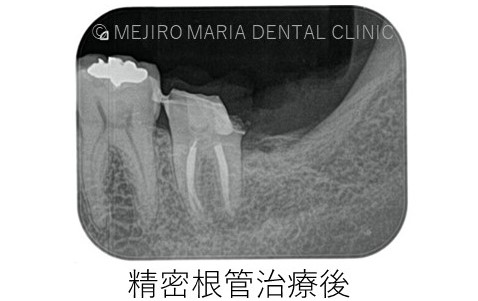

左下7番の診断は歯髄壊死が起因して起こる根尖性歯周炎であったため、まず左下7番に対して根管治療を行うことが必要でした。

しかし、当院で精密根管治療を施しましたが完全な疼痛の除去は行えませんでした。

根管の形態は非常に複雑で、根管の内部を完全に無菌化することは現在のいかなる歯科治療でも不可能です。これを歯内療法では「根管治療の限界」と言います。